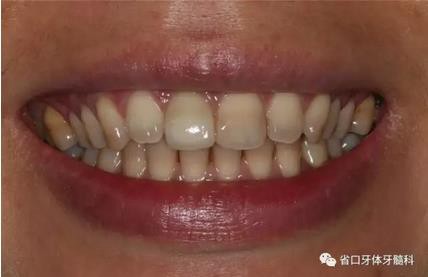

圖1 術(shù)前口內(nèi)照

圖2 術(shù)前口內(nèi)照

圖3 術(shù)前口內(nèi)照

上頜右側(cè)中切牙修復(fù)體固位良好,牙齦乳頭充盈良好,齦緣水平對稱 修復(fù)體與對側(cè)同名牙協(xié)調(diào)一致。外觀笑容美觀協(xié)調(diào)?;颊邼M意。X線檢查示 上頜右側(cè)中切牙種植體周穩(wěn)定骨質(zhì)包繞,唇側(cè)骨板>2mm,相鄰牙槽骨高度穩(wěn)定,基臺(tái)及修復(fù)體就位良好。分別根據(jù)Furhauser的PES和Bulser的WES 進(jìn)行美學(xué)評分,總分值為20,美學(xué)效果良好。